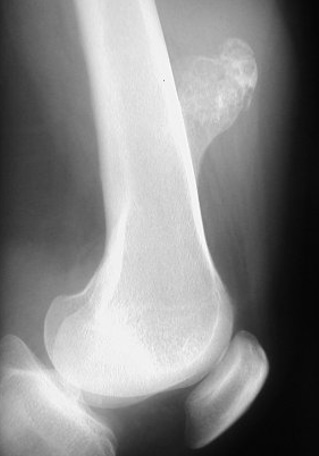

5

Q

Qual diagnóstico?

A

Projeção óssea com cortical contínua

Dx: Osteocondroma